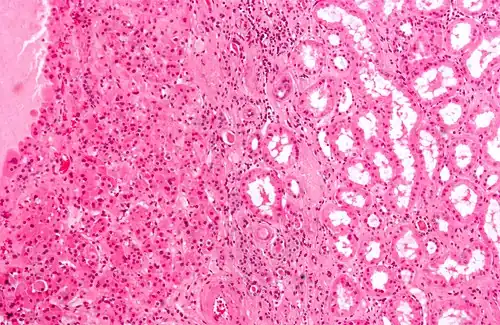

O oncocitoma renal é caracterizado pela presença de células epiteliais grandes e intensamente eosinofílicas, organizadas em um estroma de ilhotas em meio ao tecido conjuntivo frouxo; outros padrões arquiteturais incluem tubular, microcístico, macrocístico e sólido.[2] Mitoses são raras e não há mitoses atípicas, sem presença de necrose coagulativa e, alguns dos oncocitomas renais podem ter invasão perivascular ou no tecido adiposo perirrenal, ainda que seja benigno.[2]